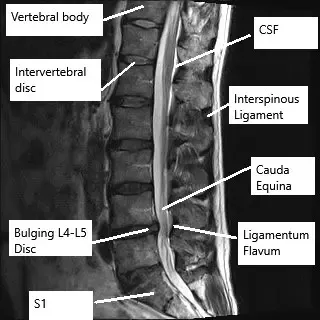

La microdiscectomía es un procedimiento quirúrgico mínimamente invasivo para ayudar a aliviar la presión causada por los nervios comprimidos conocido como ciática o radiculopatía lumbar. La ciática es causada más comúnmente por un prolapso del disco intervertebral. Durante la cirugía, el cirujano de columna extrae el material del disco intervertebral que sobresale. La recuperación tras la microdiscectomía suele ser más rápida en comparación con las discectomías abiertas y las cirugías de fusión lumbar.

Durante la cirugía, se realiza una pequeña incisión de solo unos pocos centímetros en la espalda del paciente. El cirujano luego retrae cuidadosamente la piel y los músculos de la zona lumbar. Se utiliza un endoscopio/microscopio para ayudar al cirujano a ver a través de la incisión estrecha.

Una parte de la vértebra conocida como lámina puede cortarse parcialmente para exponer el disco intervertebral. El cirujano retrae cuidadosamente las raíces nerviosas espinales y utiliza un instrumento especial para tomar pequeñas mordidas del disco intervertebral. Se extrae la parte saliente del disco intervertebral y el cirujano cierra cuidadosamente la incisión en capas.